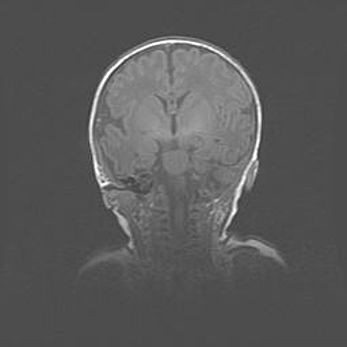

Церебральная ишемия II.

Возраст: 5 дней

Вес: 3400 г

Пол: женский

Окружность головы: 35 см

Срок гестации: 39 недель

Церебральная ишемия – это заболевание, характеризующееся недостаточностью (гипоксией) либо полным прекращением (аноксией) снабжения мозга кислородом по причине закупорки одного или нескольких сосудов. Это приводит к  что метаболическим расстройствам различной степени тяжести в тканях головного мозга, развитию коагуляционных некрозов и гибели нейронов.